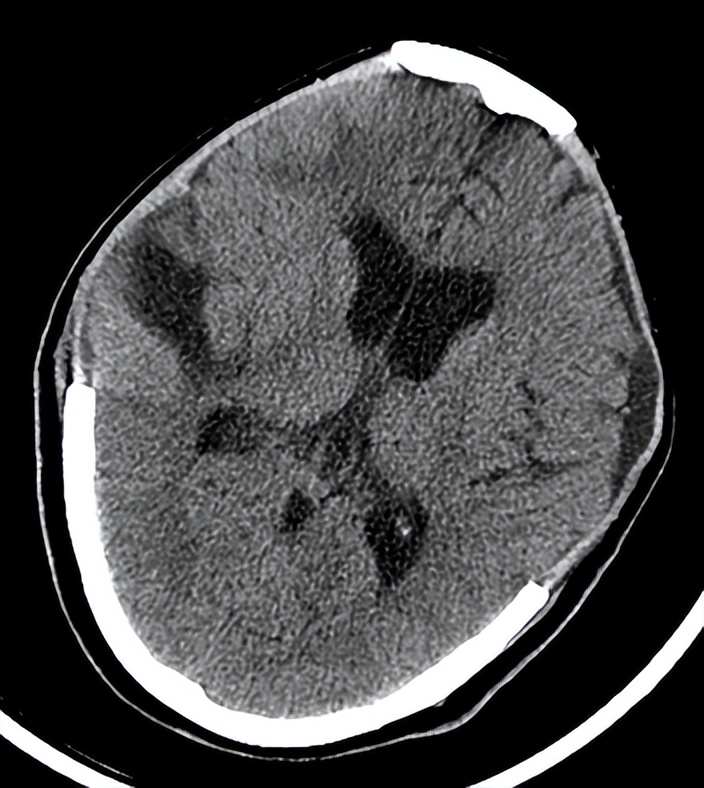

术后第三天,复查头颅CT(见下图)提示患者 脑水肿较前明显, 中线较前移位明显。目前正处在脑水肿高峰期,如果中线移位继续加重时,有必要 再次开颅 进行血肿清除。 病情危重 ,院方向患者家属交待病情,家属中有一位懂医的,都表示理解。

06-10(术后第三天复查头CT)

我被邀请查看了该患者。我先看了6月10日的头颅CT,又亲自检查了患者。

当时患者仍呈 昏迷状态 ,血压148/70mmHg,自主呼吸不规则,需有创呼吸机辅助通气,痰多,有明显痰鸣音。双侧瞳孔等大,约1.5mm,对光反射消失。脑干反射明显减弱。疼痛刺激右下肢回缩反应,左下肢无肢体回缩,双侧巴氏征阳性。

最近一次头颅CT,脑水肿明显,中线移位,双侧脑组织有继发性血肿。